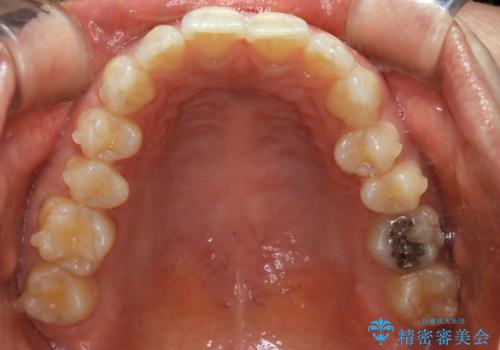

- 下の前歯のがたつきが気になるとの事でご相談にいらした患者様です。

元々はリンガルブラケットをご希望されていましたが、モニター制度を利用してインビザラインによる治療を行いました。

インビザラインFULLで奥歯の噛み合わせから改善させることで、上下の真ん中位置をしっかり合わせることが出来ました。

横顔のシルエットも改善させることができ、大変喜んでいただけました。